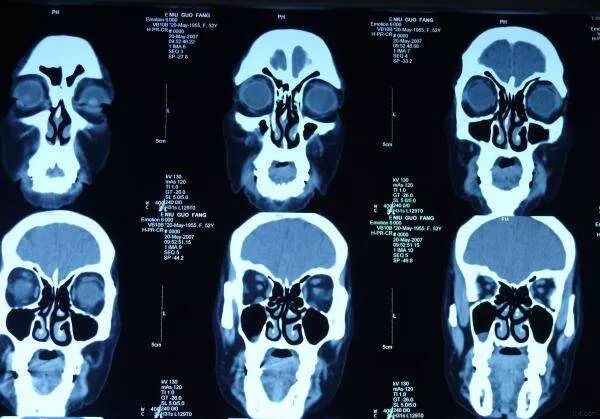

◍.CT较X线有更高的密度分辨率,对解剖的细节显示更加清晰;采用螺旋扫描方式,可获得高质量的三维图像和多平面的断面图像。

CT对胸部疾病的诊断,日益显示出它的优越性。通常采用对比剂增强扫描以明确纵隔和肺门有无肿块或淋巴结增大、支气管有无狭窄或阻塞,对原发和转移性纵隔肿瘤、淋巴结结核、中心型肺癌等的诊断,起着主要的诊断作用。随着科技的发展CT对心脏及血管的检查具有重要意义。心脏方面主要是心包病变的诊断。心腔及心壁的显示。血管方面冠状动脉的钙化、大血管壁的钙化及动脉瘤改变等,CT检查可以很好显示。